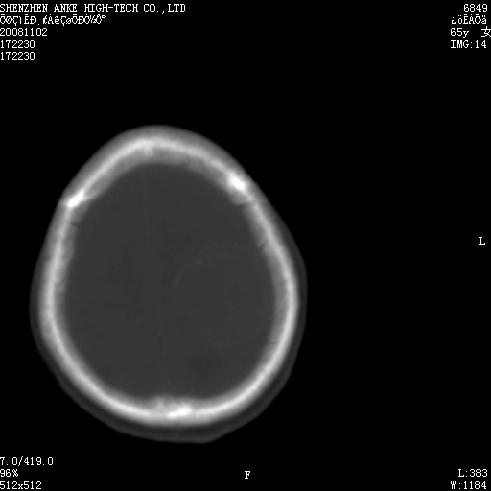

患者,女性,65岁,突发右侧肢体无力伴头痛,恶心、呕吐3小时.

1 左侧顶区圆形病灶,内可见钙化,考虑脑膜瘤,建议增强。2 左侧侧脑室病变,考虑神经上皮囊肿。

1)左侧顶区脑膜瘤可能性大;建议必要时行进一步检查。2)左侧脑室积水。

左顶部脑膜瘤,左侧侧脑室蛛网膜囊肿,建议增强.